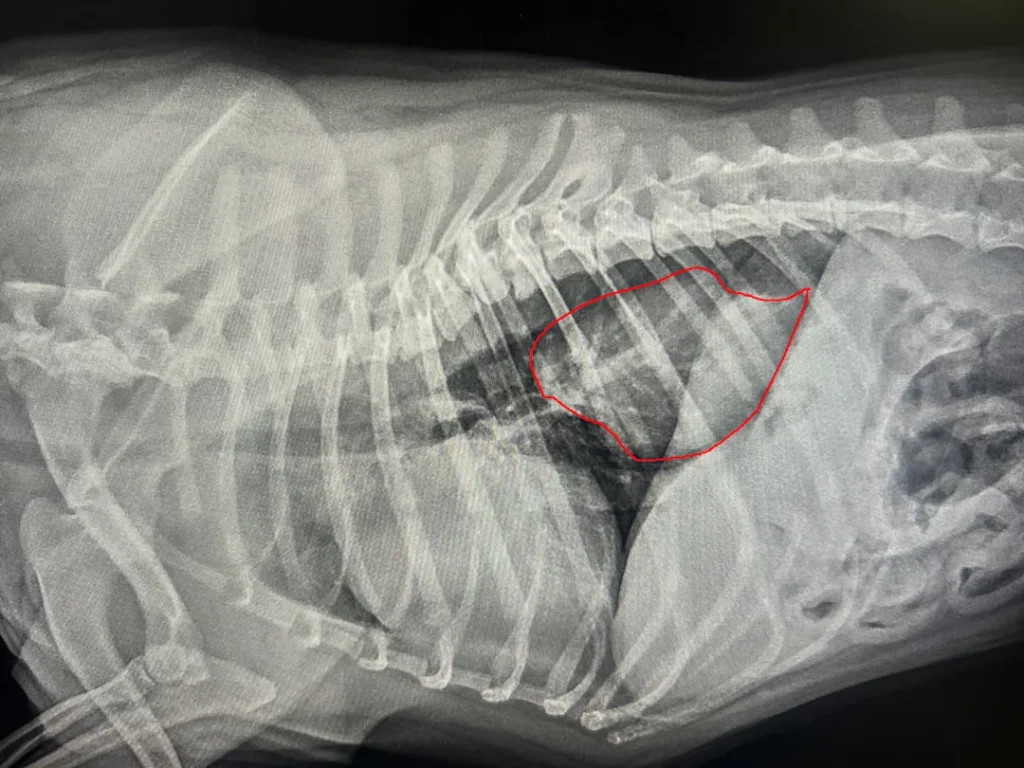

Diaphragmatic Hernias:

diaphragmatic hernia mcmichael sized

This is an internal tear in the diaphragm—the muscle separating the chest from the abdomen. Usually, this is caused by trauma, like a car accident, and it’s a critical emergency because organs can move into the chest and compress the lungs.